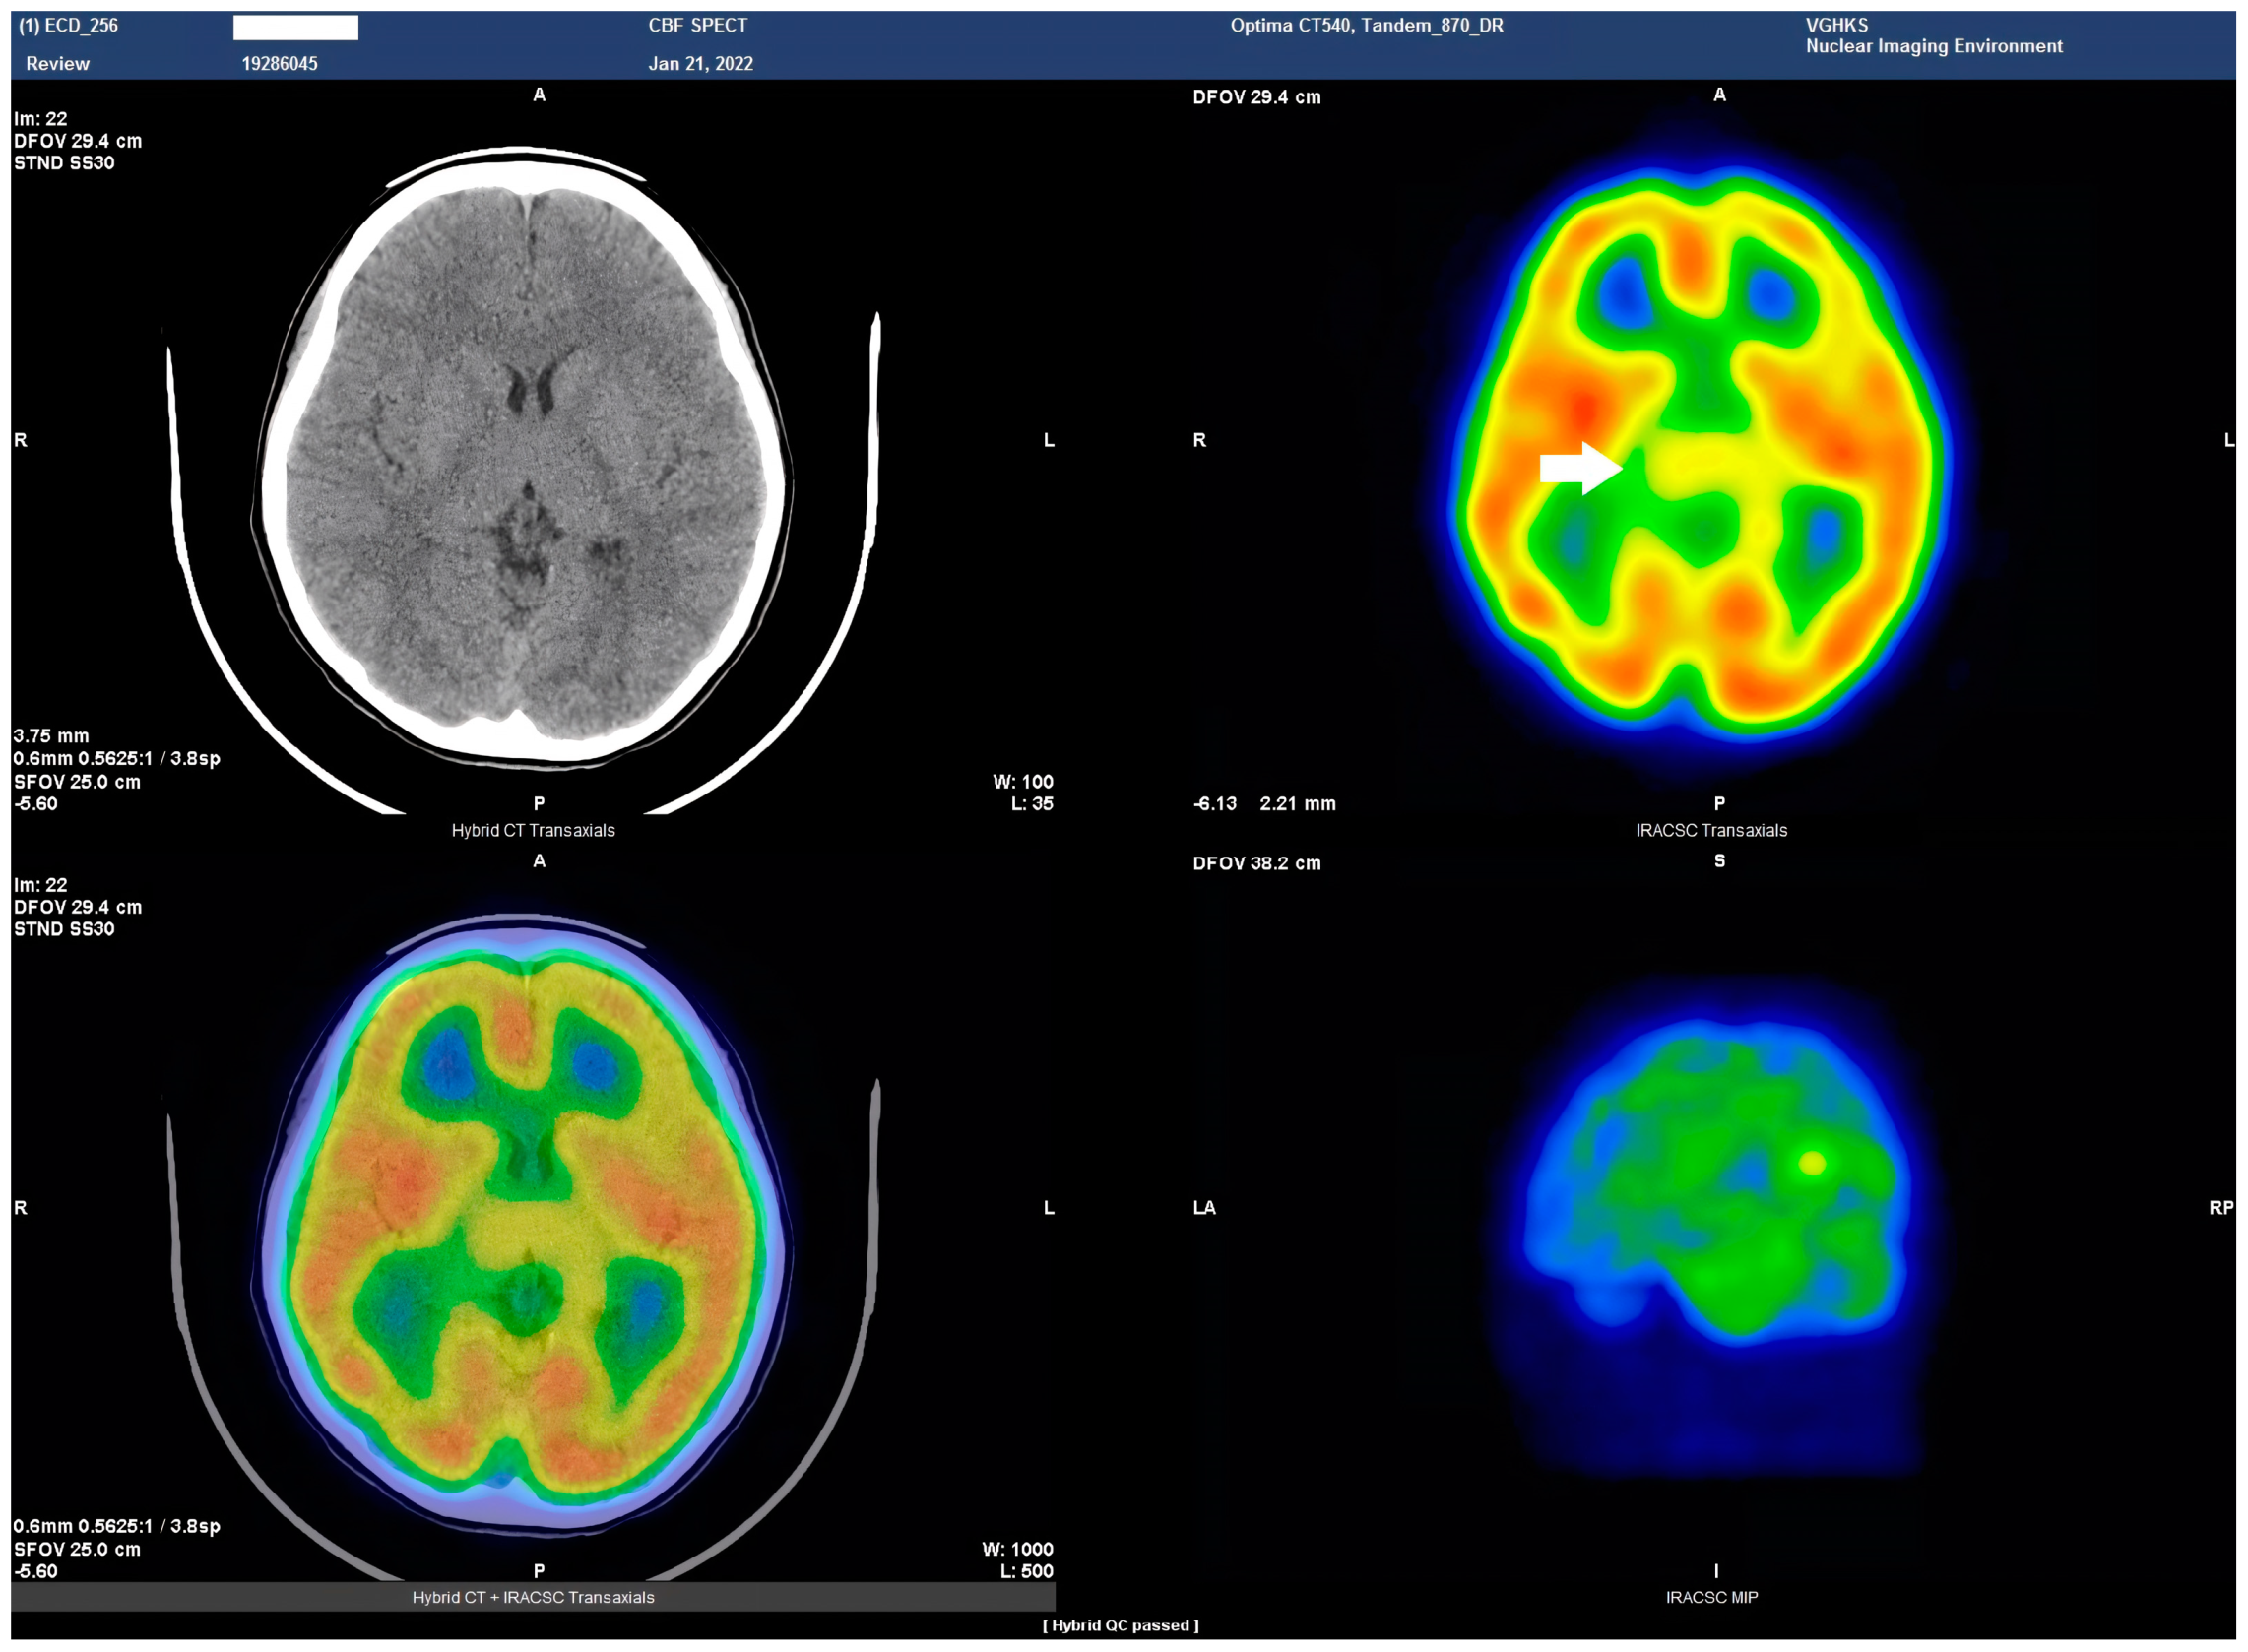

HSAN4 is a rare genetic disorder with a complex clinical presentation. Our hypothesis that the CNS might be implicated in this condition gained substantial support from the clinical manifestations observed in our patient. The presence of spasticity in her feet and a strong positive Babinski’s sign, which are characteristics commonly found in patients with upper motor neuron (UMN) lesions [16], prompted us to explore the potential involvement of the central nervous system (CNS) in HSAN4. To investigate this novel aspect, we employed Tc−99m ECD SPECT imaging for assessing cerebral blood flow and revealing perfusion deficits within the brain [23]. This study represents the pioneering visualization of brain perfusion abnormality in an HSAN4 patient, and the findings are nothing short of groundbreaking. Our Tc−99m ECD SPECT imaging revealed multiple areas within the CNS with perfusion deficits. Notably, these deficits were observed in the cerebellum (Figure 2), thalamus (Figure 3), and postcentral gyrus of the parietal lobe (Figure 4 and Figure 5). These findings suggest that HSAN4 has the potential to affect not only the peripheral nervous system (PNS) but also the CNS, ushering in a new era in our understanding of this complex disorder. One of the most significant and intriguing aspects of our findings is the localization of these deficits in the postcentral gyrus and thalamus. These regions play pivotal roles in processing pain signals transmitted from the spinothalamic and spinoreticular tracts [24]. The spinothalamic and spinoreticular tracts are the central pathway for nociceptive signals, conveying pain information from the peripheral nervous system to the cerebral cortex. The former pathway originates from the dorsal root ganglia, traverses the dorsal horn of the spinal gray matter, proceeds to the ventral posterolateral nucleus of the thalamus, and finally reaches the posterior limb of the internal capsule. The latter tract also handles nociceptive signals, routing them to the thalamus and postcentral gyrus [25,26]. The perfusion deficits we observed in these crucial pain-processing areas offer a profound and novel perspective on explaining the pain insensitivity characteristic of HSAN4 patients. While previous research has primarily focused on the peripheral mechanisms of pain insensitivity, our study provides compelling evidence that the origin of this phenomenon might extend beyond the peripheral nervous system.

In essence, pain insensitivity in HSAN4 involves intricate CNS mechanisms. The perfusion deficits in the thalamus and postcentral gyrus shed light on how HSAN4 may disrupt these critical pathways, leading to the observed pain insensitivity. This revelation challenges conventional thinking and highlights the importance of considering both peripheral and central components in our understanding of HSAN4.

Figure 4. Coronal view of the Tc−99m ECD brain perfusion SPECT images. A decreased uptake in the tracer can be observed in the parietal area, especially in the postcentral gyrus (arrow).

Figure 5. Sagittal view of the Tc−99m ECD brain perfusion SPECT images. A decreased uptake in the tracer can be observed in the parietal area, especially in the postcentral gyrus (arrow).